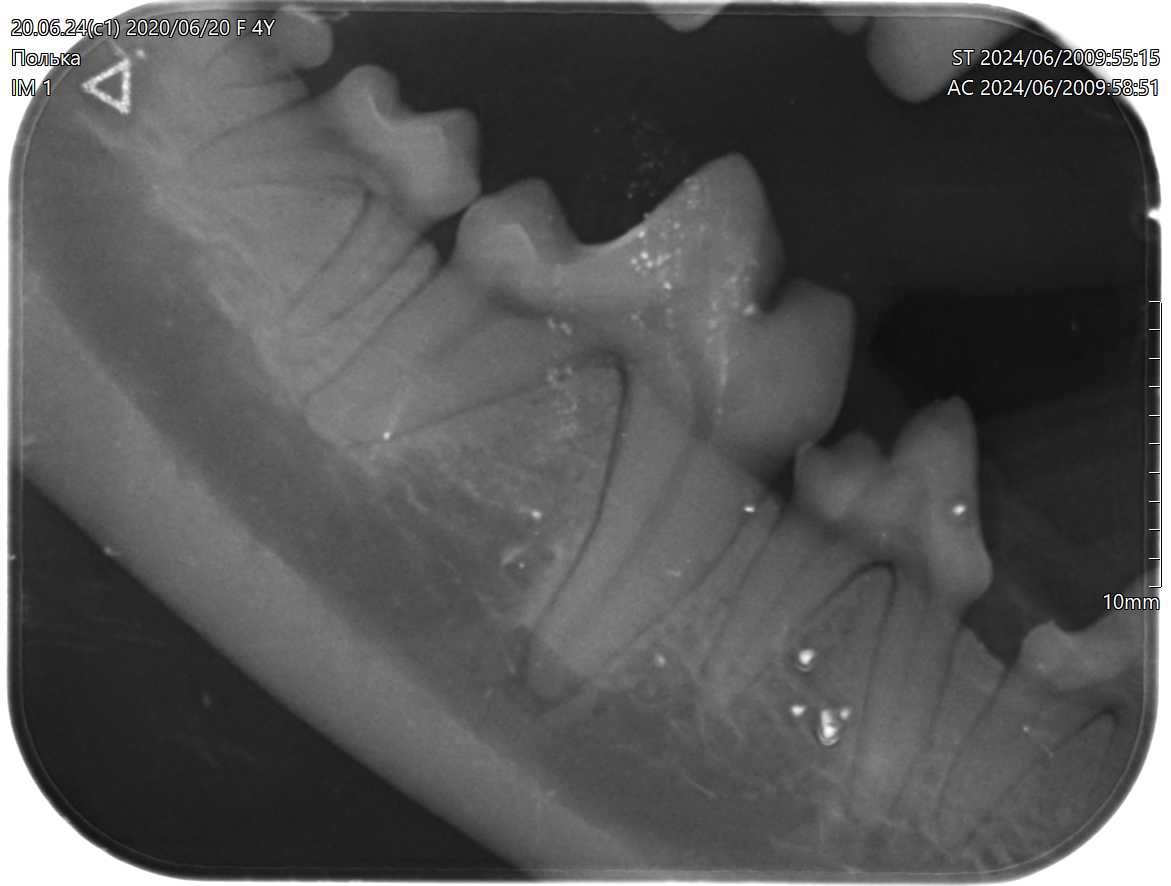

Здоровый пародонт беспородной собаки, 4г